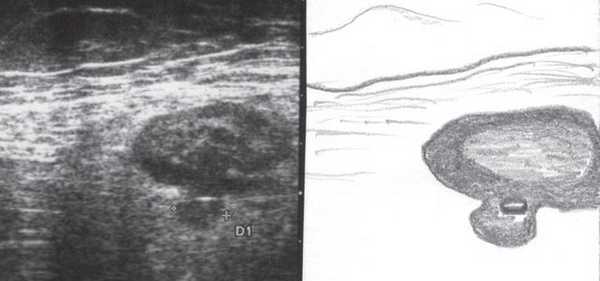

При УЗИ были выявлены диффузные изменения печени и поджелудочной железы, признаки хронического бескаменного холецистита, ангиомиолипома левой почки (без динамики за несколько лет), состояние после экстирпации матки с придатками. В левой подвздошной области соответственно зоне максимальной пальпаторной болезненности на протяжении 9 см отмечалось утолщение стенок толстой кишки до 6-7 мм (рис. 1). Перистальтика кишки отсутствовала, гаустрация была слабо выражена, при этом визуализировалось несколько болезненных при надавливании датчиком выпячиваний пониженной эхогенности, размером от 7 до 20 мм (рис. 2, а, б) с тонкой стенкой до 0,9-1,1 мм и наличием в некоторых из них фрагментов кишечного содержимого и газа (рис. 3, а, б).

Рис. 1. Эхографическая картина дивертикулита. Трансабдоминальное исследование линейным датчиком 7,5 МГц.

"Симптом пораженного полого органа".

Рис. 2. Эхографическая картина дивертикулита. Трансабдоминальное исследование линейным датчиком 7,5 МГц.

а) Продольный срез.

б) Поперечный срез.